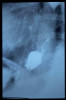

TC exostosis occipital congénica.

TC exostosis occipital congénita.